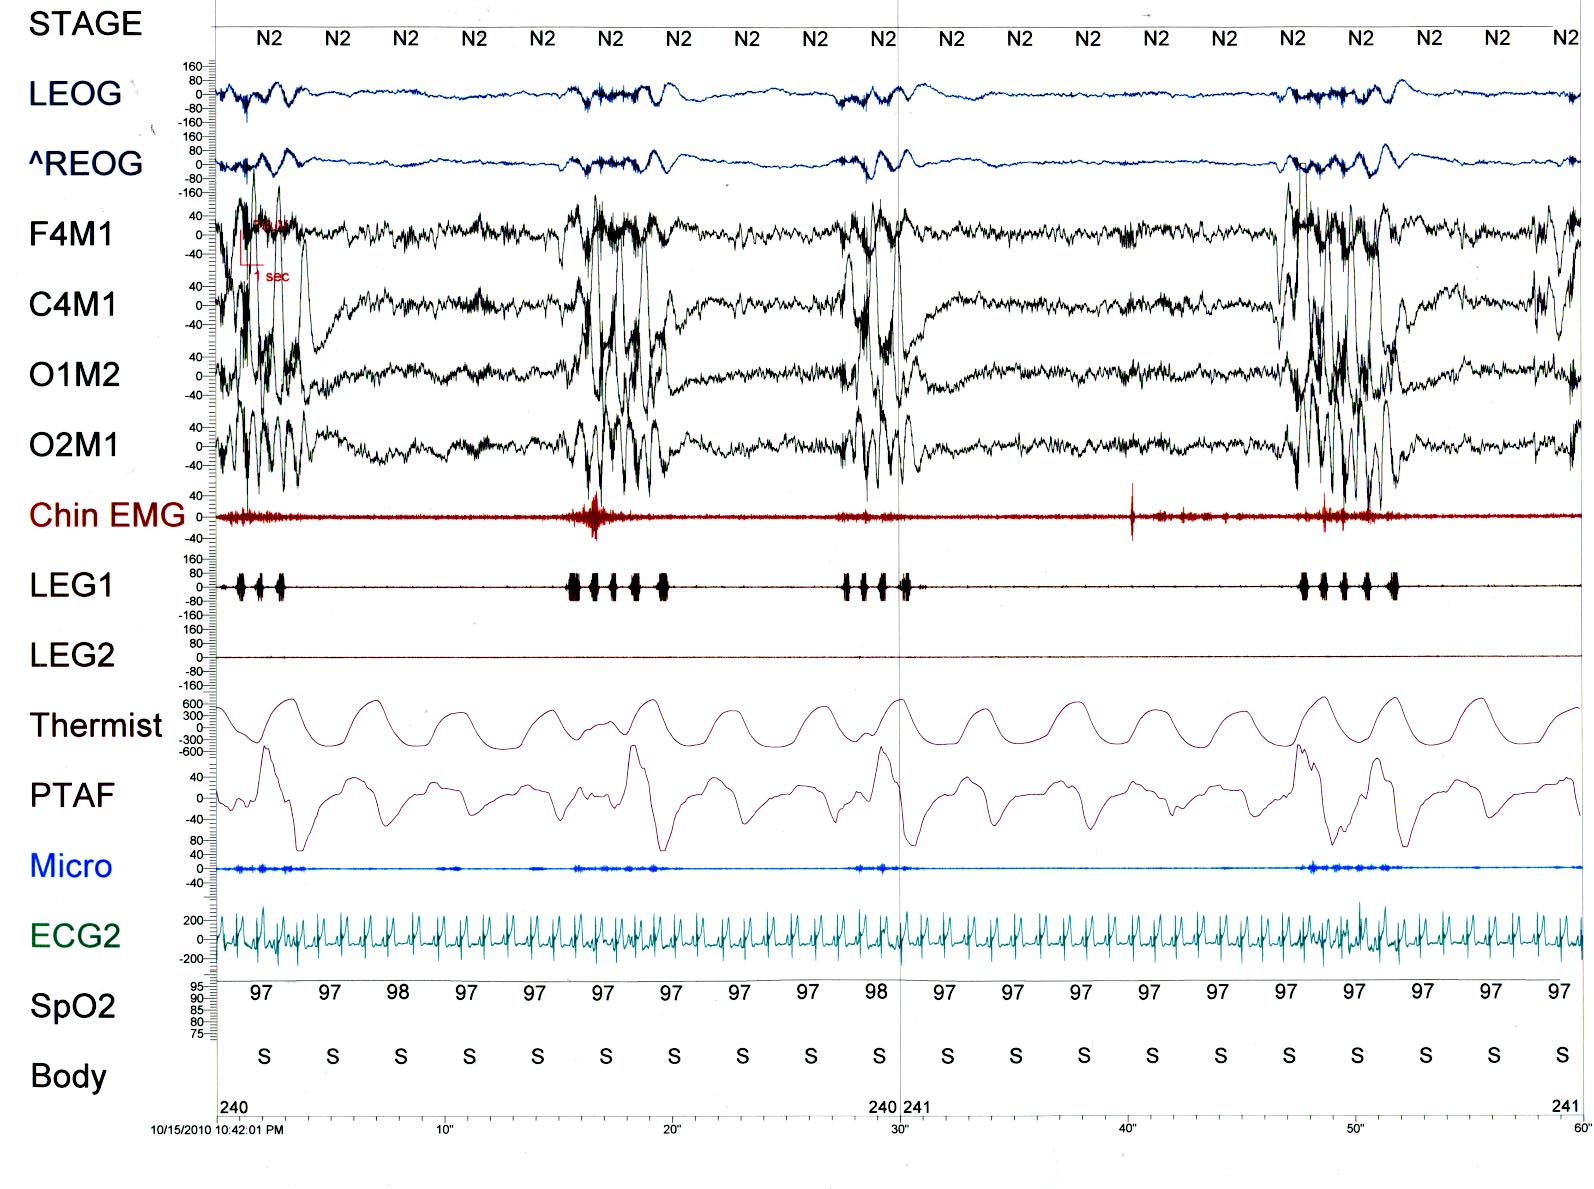

What significant finding is seen in the PSG tracings?

Rhythmic Movement Disorder [Head Rolling]

In the PSG tracing we see episodes of 1 Hz. activity across the EEG and leg leads corresponding to movement in the EMG, EKG artifact and chest and abdomen with enhanced PTAF. The frequency corresponds to video monitoring showing head movement consistent with Rhythmic Movement Disorder.